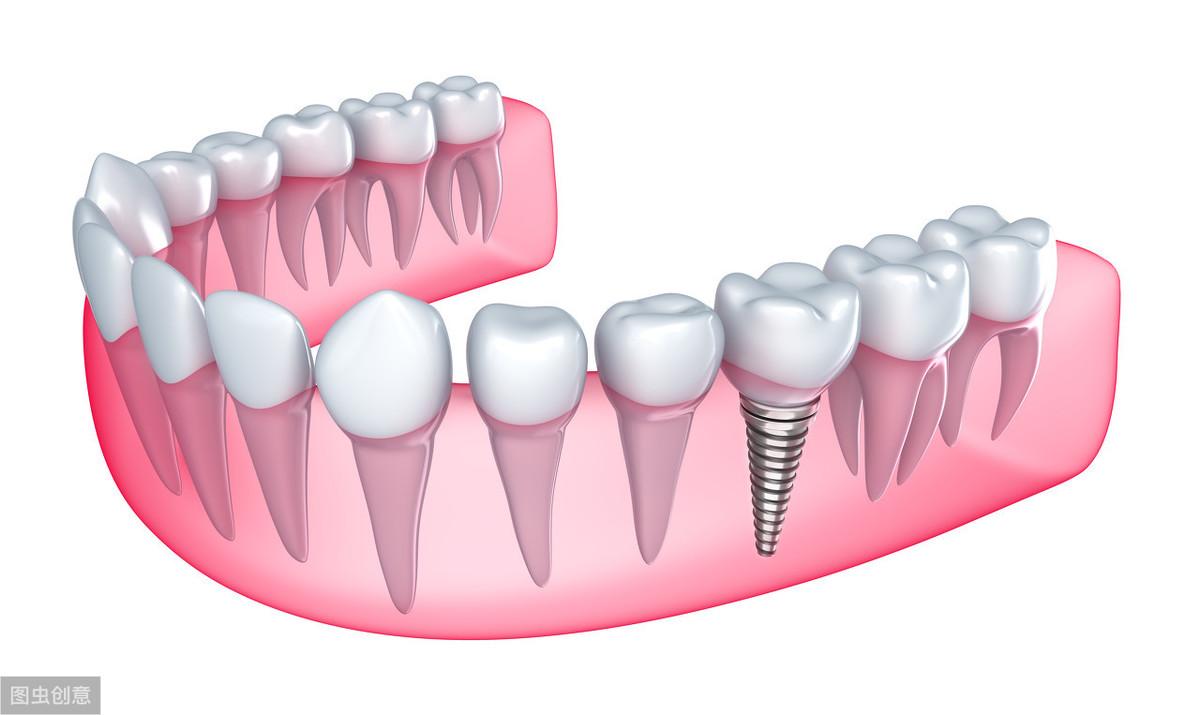

種植牙技術(shù)是近幾十年出現(xiàn)在大眾視野中的一種修復(fù)缺失牙體的方法。一顆完整的種植牙體由三部分組成:種植體、基臺、人工牙冠。

手術(shù)過程就是將種植體植入患者的牙體缺失處,待其傷口愈合,種植體與牙槽骨結(jié)合牢固后,將基臺安裝在種植體上,再將人工牙冠安裝在基臺上,形成完整而堅固的人工牙體。

種植牙技術(shù)就像在缺失牙體處種一顆新的牙齒,能夠和牙槽骨結(jié)合,做種植牙能有預(yù)防牙槽骨萎縮,這是普通的假牙無法做到的,而且種植牙體不依附周圍鄰牙,對鄰牙不造成任何負(fù)擔(dān),所以相對其他修復(fù)手段,不僅更為牢固不易松動,且使用壽命長,果好。